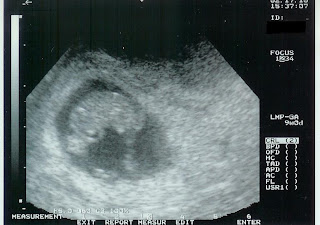

We went today for our first appointment. All is well. My calculations put me at 8 weeks 6 days, the ultrasound measurements put me at 8 weeks 3 days; this makes the estimated due date some time between September 23rd and 26th. The doctor commented 4 or 5 times on Jellybean's heart rate, which was 172. That was comforting. At this point the plan is for me to be seen every 2 weeks. We go back in two weeks for a physical, and then have another ultrasound as part of the first trimester screen on March 15th. It was a good appointment, and we seem to be on the same page as the doc with the monitoring plan. Here is the picture that we got of Jellybean today...